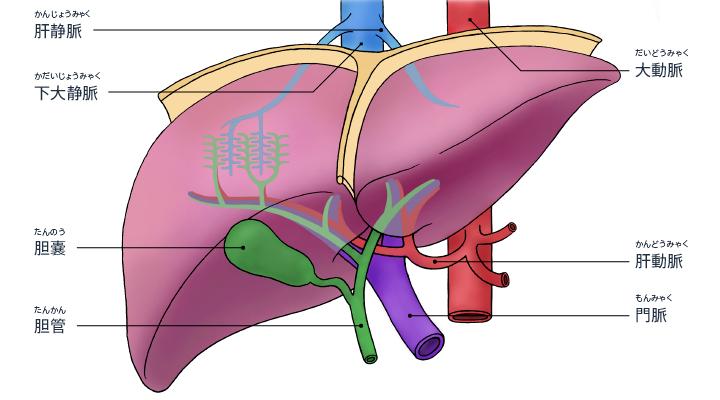

胆道系统的组成

胆道系统组成:由肝内胆管、肝外胆管、胆囊及 Oddi 括约肌组成。

胆囊:分为底、体、颈三部,为囊性器官,呈梨形,位于肝脏脏面的胆囊窝内,相当于肝右叶与肝方叶之间。长 8~12 cm,宽 3~5 cm;容积 40~60 ml。胆囊管、肝总管及肝脏脏面三者构成的三角形区域称为胆囊三角 (又叫 Calot 三角、卡洛氏三角 Calot's triangle、hepatobiliary triangle 、胆囊动脉三角)

胆囊管:是连接胆囊与胆总管之间的管道,一般长约 2.5~4 cm,管径约 0.2~0.3 cm。胆囊管具有多种的解剖学变异。

肝总管:左、右肝管出肝后,在肝门部汇合形成肝总管。肝总管直径为 0.4~0.6 cm,长约 2~4 cm,位于肝十二指肠韧带中,其下端与胆囊管汇合形成胆总管。

胆总管:由肝总管与胆囊管在肝十二指肠韧带中汇合形成,全长约 7~9 cm,直径 0 .6~0 .8 cm,直径一般不超过 1 cm。分为四段:十二指肠上段、十二指肠后段、胰腺段、十二指肠壁内段。

大多数人胆总管与主胰管在肠壁内汇合形成一共同通道,并膨大形成胆胰壶腹。另有 15%~20% 的胆总管与主胰管分别开口于十二指肠。Oddi 括约肌主要包括胆管括约肌、胰管括约肌和壶腹括约肌,它具有控制和调节胆总管和胰管的排放,以及防止十二指肠内容物反流的重要作用。

正常肝内的胆管与肝动脉及门静脉的肝内分支相互伴行,肝右叶右前、后叶肝管在肝门静脉右支前上方汇合组成右肝管,肝左叶左外上、下段肝管于肝门静脉左支横部的前上方汇合构成左肝管,肝总管下行于肝十二指肠韧带内,在韧带内胆囊管与肝总管以锐角汇合形成胆总管,与十二指肠大乳头处胆总管与主胰管汇入肠管内。肝内胆管主要对由肝细胞产生的胆汁起到输送作用,胆囊管是连接胆囊与肝外胆管的重要结构,胆总管主要是确保胆汁可以由胆囊腔进入肠道内。